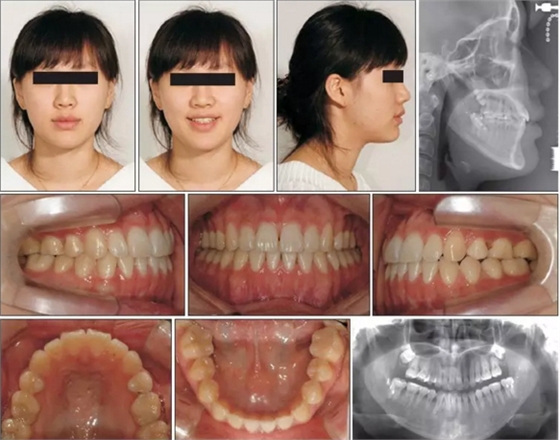

患者獲得了顯著的面型改變。前突的頦部獲得了適當(dāng)?shù)暮笠啤O骂M后退了大約10mm。頜骨矢狀向關(guān)系獲得了改善(Pog to N-perpendicular, −0.5 mm; ANB, −0.1°),面部不對(duì)稱問題被糾正。獲得了I類尖牙關(guān)系和II類磨牙關(guān)系,獲得了理想的覆合覆蓋。獲得了一致的牙列中線。

正畸治療6年后,患者沒有不適且維持了穩(wěn)定的咬合關(guān)系。